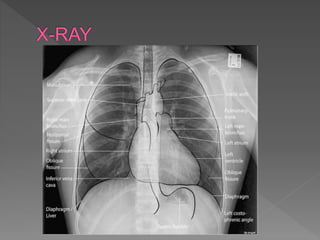

 A - Airway

 Trachea is visible and in midline

 Trachea gets pushed away from abnormality,

e.g. pleural effusion or tension pneumothorax

 Trachea gets pulled towards abnormality, e.g.

atelectasis

 Trachea normally narrows at the vocal cords

 View the carina, angle should be between 60 –

100 degrees

 Visibility of the Trachea in the Midline

 The trachea is normally narrower by the region of the vocal cords .

 During certain abnormalities the trachea reacts by

 Moving away as in thesec onditions :Pleural Effusion or Pneumothrox

 Pulled towards , as in these conditions: Atlectasis

 Carina Angle is normally between 60 – 100 degrees with the Right Bronchi

being steeper.

 Abnormalities that may increase the angle such as Left Atrial Enlargement and

Lymph Node Enlargements.

 The integrity of the Brochi stems and be worry of any any abnormalities such

as foreign bodies and obstructions of the airway

 Endotracheal Tubes: should be placed 3 – 4cm above the Carina

 Mediastinum

 Must be measured and be equidistant from the left to the right side.

 Observe for the presence of any mass lesions , inflammation

 B – Bones

 Check for fractures, dislocation, subluxation,

osteoblastic or osteolytic lesions in clavicles,

ribs, thoracic

 Spine and humerus including osteoarthritic

changes

 At this time also check the soft tissues for

subcutaneous air, foreign bodies and

surgical clips

 C - Cardiac

 Check heart size and heart borders

 Heart position –⅔ to left, ⅓ to right

 Heart size – measure cardiothoracic ratio on PA

film (normal <0.5)

 Heart borders – R) border is R) atrium, L)

border is L) ventricle & atrium

 D – Diaphragm

 Right hemi-diaphragm o

 Should be higher than the left o(~2.5cm / 1

intercostal space)

 If much higher, think of effusion, lobar

collapse, diaphragmatic paralysis o

 If you cannot see parts of the diaphragm,

consider infiltrate or effusion

 E – Effusion

 Effusions o Look for blunting of the

costophrenic angle

 Identify the major fissures, if you can see

them more obvious than usual, then this

could mean that fluid is tracking along the

fissure

 Check out the pleura

 Thickening, loculations, calcifications and

pneumothorax